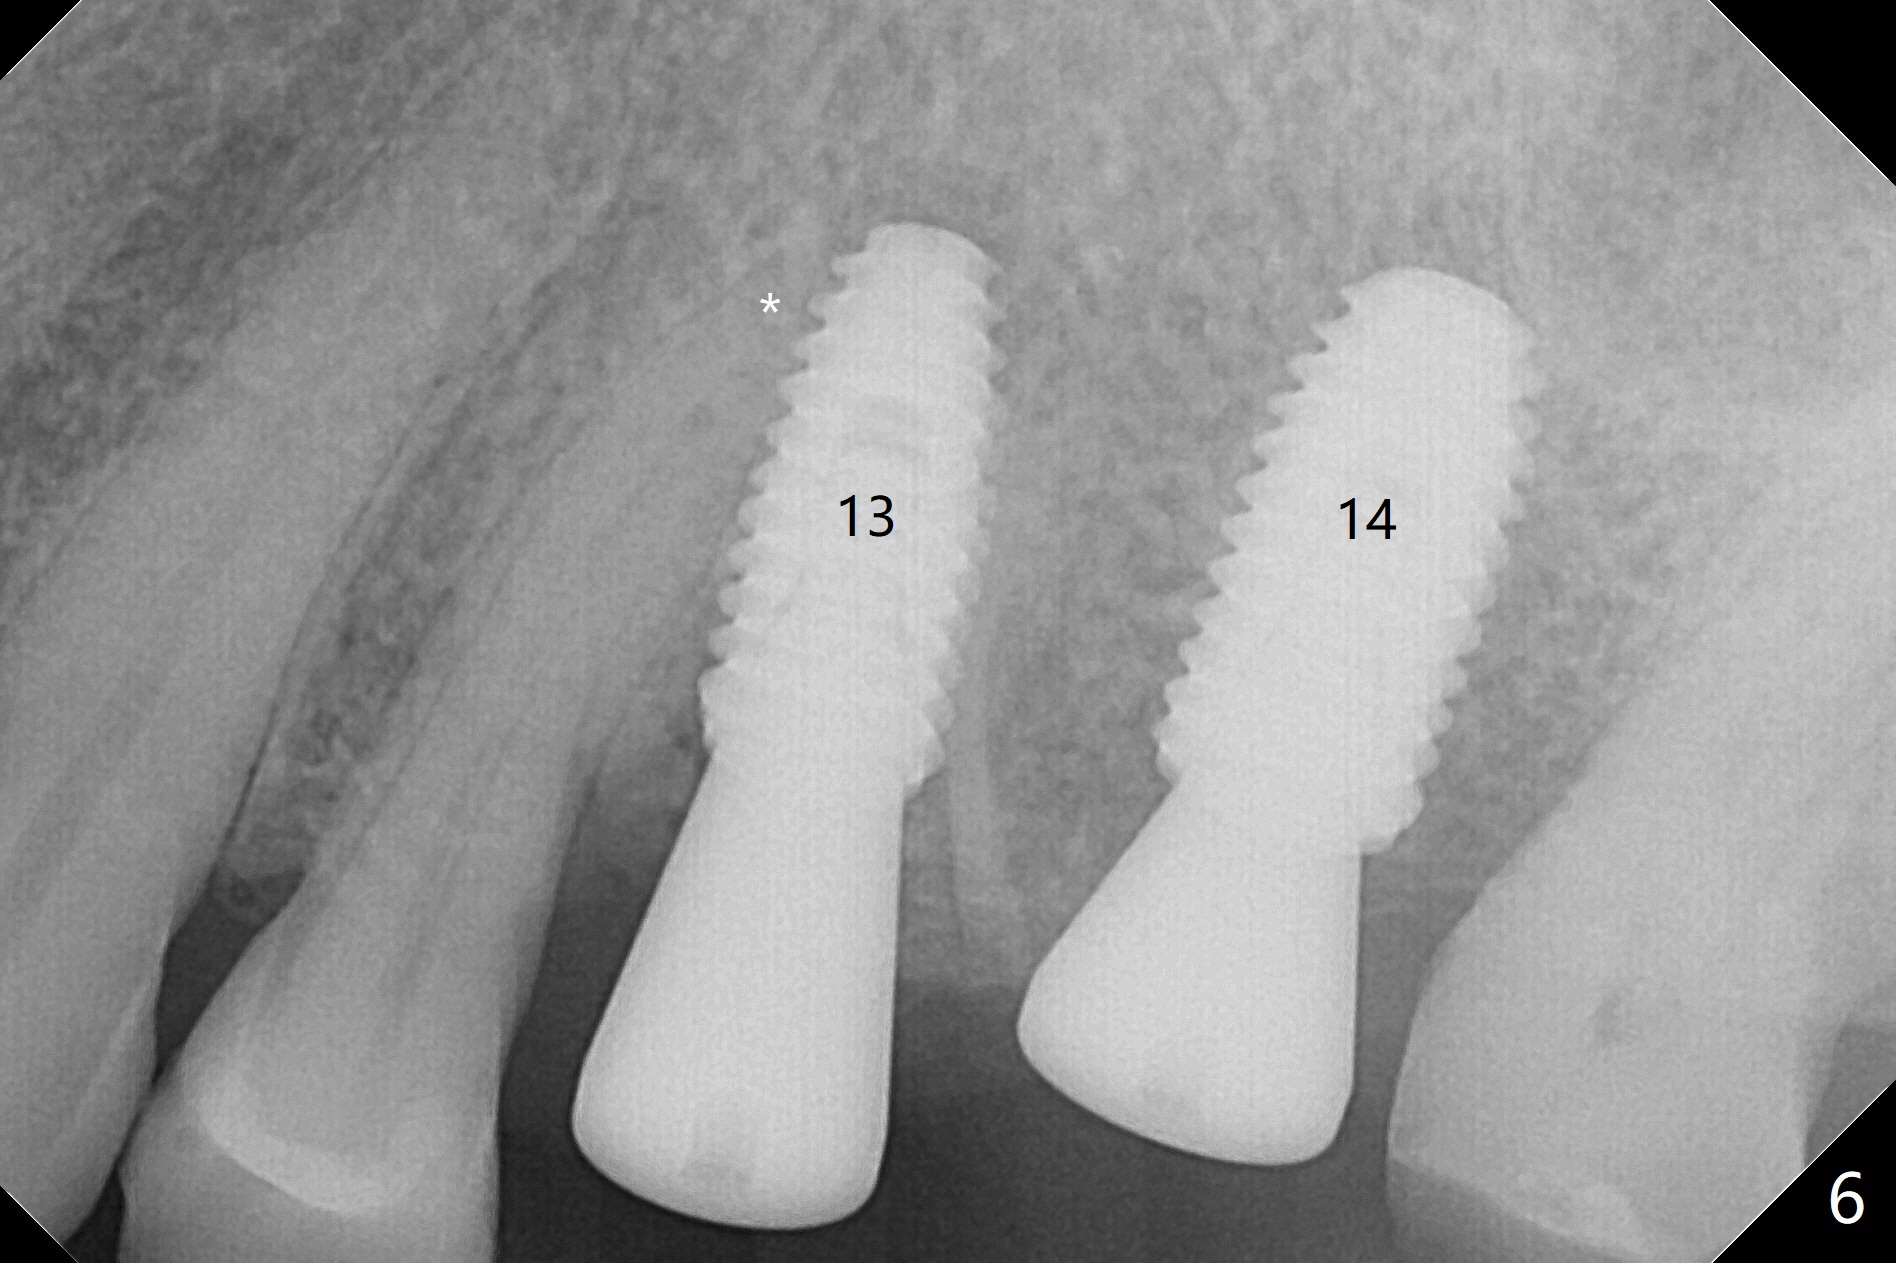

After extraction of the tooth #13 residual root, the bone in the distal wall of the socket looks white. Intraop PA rules out root structure (Fig.1 *). Osteotomy is conducted according to drill sequence. Bitewings are taken to check implant placement level (Fig.2,3). Following implant level adjustment and healing abutment installment (Fig.4,5 (*: bone graft)), the implant at #13 is found to be close the root of #12 (Fig.6 *), i.e., not parallel to the implant at #14. Introspectively, 2.2x10 mm drill seems to be long. When it touches the bone, the cylinder portion of the drill (Fig.7 red) does not engage into the sleeve (green). When it goes into the bone, it may have been deflected mesial due to the slope of the distal wall of the socket (hard bone, Fig.8 open arrow)). If a shorter drill (such as 2.2x7.3 or 8.5 mm) were used (Fig.9), the deflection would be minimal if drilling is slow (Fig.10). CT taken 1 week postop shows that the implant at #13 is approximately 1 mm near the root of the tooth #12, but the neurovascular bundle to the latter seems not to have been interrupted (Fig.11,12). The buccopalatal trajectory at #14 is within normal limit (Fig.11,13 (B: buccal)). There is no periapical radiolucency at #12 five months postop (Fig.14). However the cemented abutments are incompletely seated (<). The patient is reluctant to return for impression 17 months postop (due to coronavirus); with attention, the same abutment at #13 is reseated completely; an abutment with longer cuff and narrower diameter is also seated completely (Fig.15).